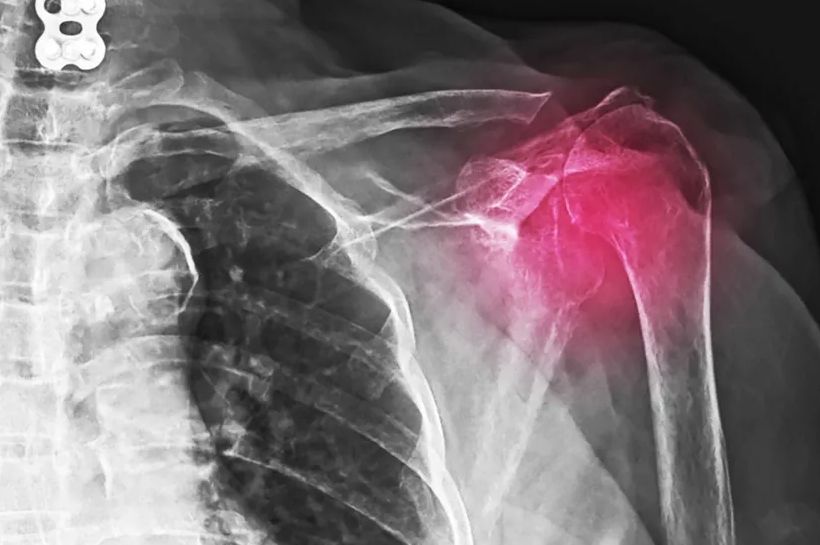

Ramena – Naslage kalcijuma u ramenima mogu da izazovu bol i nelagodnost kada se krećemo, ali i smanjen obim pokreta. Ali, ponekad kalcifikacija ramena ne izaziva simptome. Ljekar može da ih otkrije tokom testa snimanja za sasvim nepovezano stanje. Stanje koje se naziva kalcifikacioni tendinitis razvija se kada se naslage kalcijuma nakupljaju u tetivama ili mišićima. Kalcifikacioni tendinitis može da se javi bilo gdje u tijelu, ali najčešće pogađa rotatornu manžetnu. Rotatorna manžetna je grupa mišića i tetiva koje okružuju kuglu ramenog zgloba i drži kuglu ramenog zgloba u ramenskoj čašici.